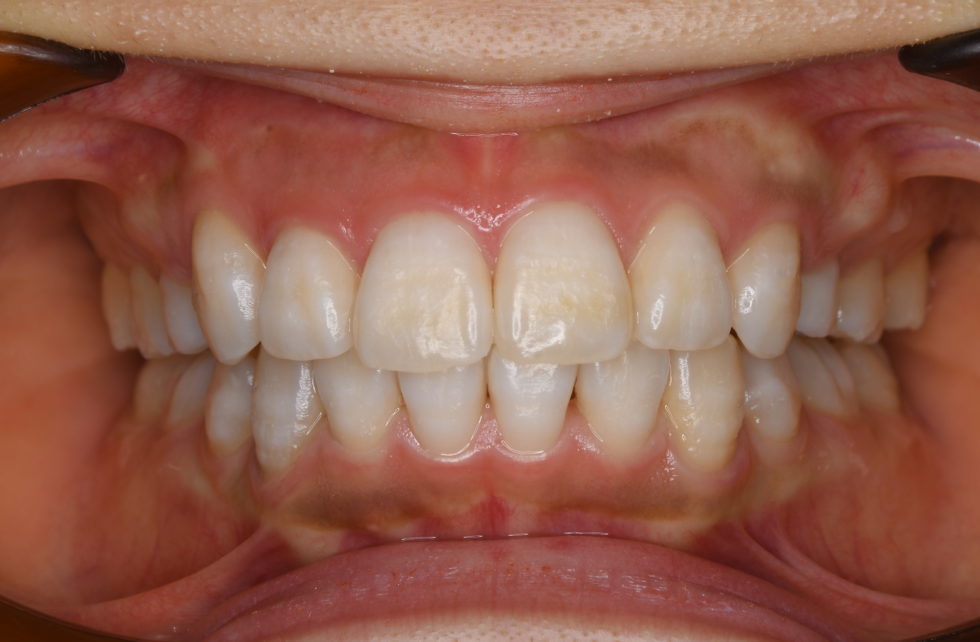

初診時年齢20歳の女性 上顎右側犬歯の低位唇側転位を主訴として来院された。

上顎右側犬歯は完全に歯列から外れて生え、また、左側中切歯は約7㎜突出していた。下顎前歯にも著しい叢生があった。セファロ分析の結果、著しい叢生を伴う骨格性上顎前突と診断し上下顎小臼歯を抜歯していただき、矯正用アンカースクリューを併用し、マルチブラケット装置を使用して動的治療を行った。矯正用ゴムなどの使用状況も良く良好な結果が得られた。歯の痛みはあったが2、3日で普通の食事ができるため過度な心配は必要がない。また、歯が動いていることが目に見えて分かるためモチベーションが保てたとおっしゃっていた。

動的治療期間2年0カ月(調整来院20回)